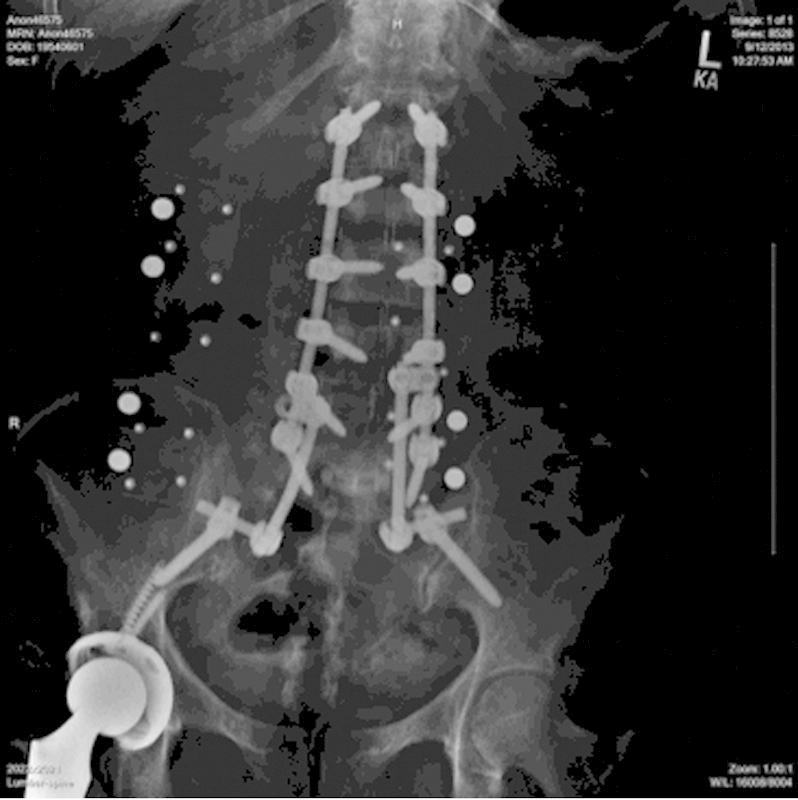

研究设计案例报告。目的本研究的目的是提出一个不寻常的情况下,59岁的妇女与复发的无菌术后血清肿。方法术后观察1例患者在创面闭合前先在软组织内放置预防性万古霉素粉2 g (1 g与后外侧骨融合术联合使用,1 g放置于软组织内)进行多节段腰椎前后路融合术的并发症或不良反应。在初始手术后的6个月内监测患者的进展。术后6周,患者摔倒,疼痛加重。磁共振成像、计算机断层扫描和x线显示骶骨骨折移位,大量硬膜外积液,腰椎手术部位硬膜囊严重受压(L3-5)。结果根据上述影像学检查和患者进行性神经功能缺损,在6周的随访中明显需要紧急手术干预。引流和检查硬膜外积液,同时治疗移位性骶骨骨折(S1-S2)。患者术后过程平稳,背部疼痛和神经功能障碍得到缓解;然而,复发的硬膜外积液需要连续穿刺混淆了患者的临床表现。结论由于该血肿的复发性不常见,其液体收集和形成的原因尚不清楚。由于缺乏骨形态发生蛋白的使用,并且很少有可解释的混杂变量,对局部万古霉素粉末的急性过敏反应是可能的病因。建议对更大的患者群体进行分析,比较预防性万古霉素粉末的术后不良反应。

Study Design Case report. Objective The objective of this study was to present the unusual case of a 59-year-old woman with a reoccurring sterile postoperative seroma. Methods A patient was observed postoperatively for any complications or adverse side effects resulting from an initial multilevel anterior/posterior lumbar fusion surgery where 2 g (1 g combined with the bone graft used for posterolateral fusion and 1 g placed in the soft tissues) of prophylactic vancomycin powder was placed within the soft tissues posteriorly before wound closure. The patient's progress was monitored through 6 months following the initial procedure. Six weeks postoperatively, the patient sustained a fall and had increased pain. Magnetic resonance imaging, computed tomography, and X-rays demonstrated a displaced sacral fracture, a large epidural fluid collection, and severe compression of the thecal sac at the lumbar operative sites (L3-5). Results On the basis of the aforementioned imaging studies and the patient's progressive neurologic deficit, it was apparent at the 6-week follow-up that emergent surgical intervention was necessary. Drainage and examination of an epidural fluid collection along with treatment of a displaced sacral fracture (S1-S2) were performed. The patient had an uneventful postoperative course with resolution of her back pain and neurologic deficit; however, recurrence of the epidural fluid collection requiring serial aspirations confounded the patients' clinical presentation. Conclusions With the recurrent nature of the seroma being unusual, the cause of the fluid collection and formation is undetermined. With lack of bone morphogenetic protein usage, and few confounding variables accountable, an acute allergic response to topical vancomycin powder is a possible etiology. Analysis with larger patient populations comparing postoperative adverse effects of prophylactic vancomycin powder is recommended.